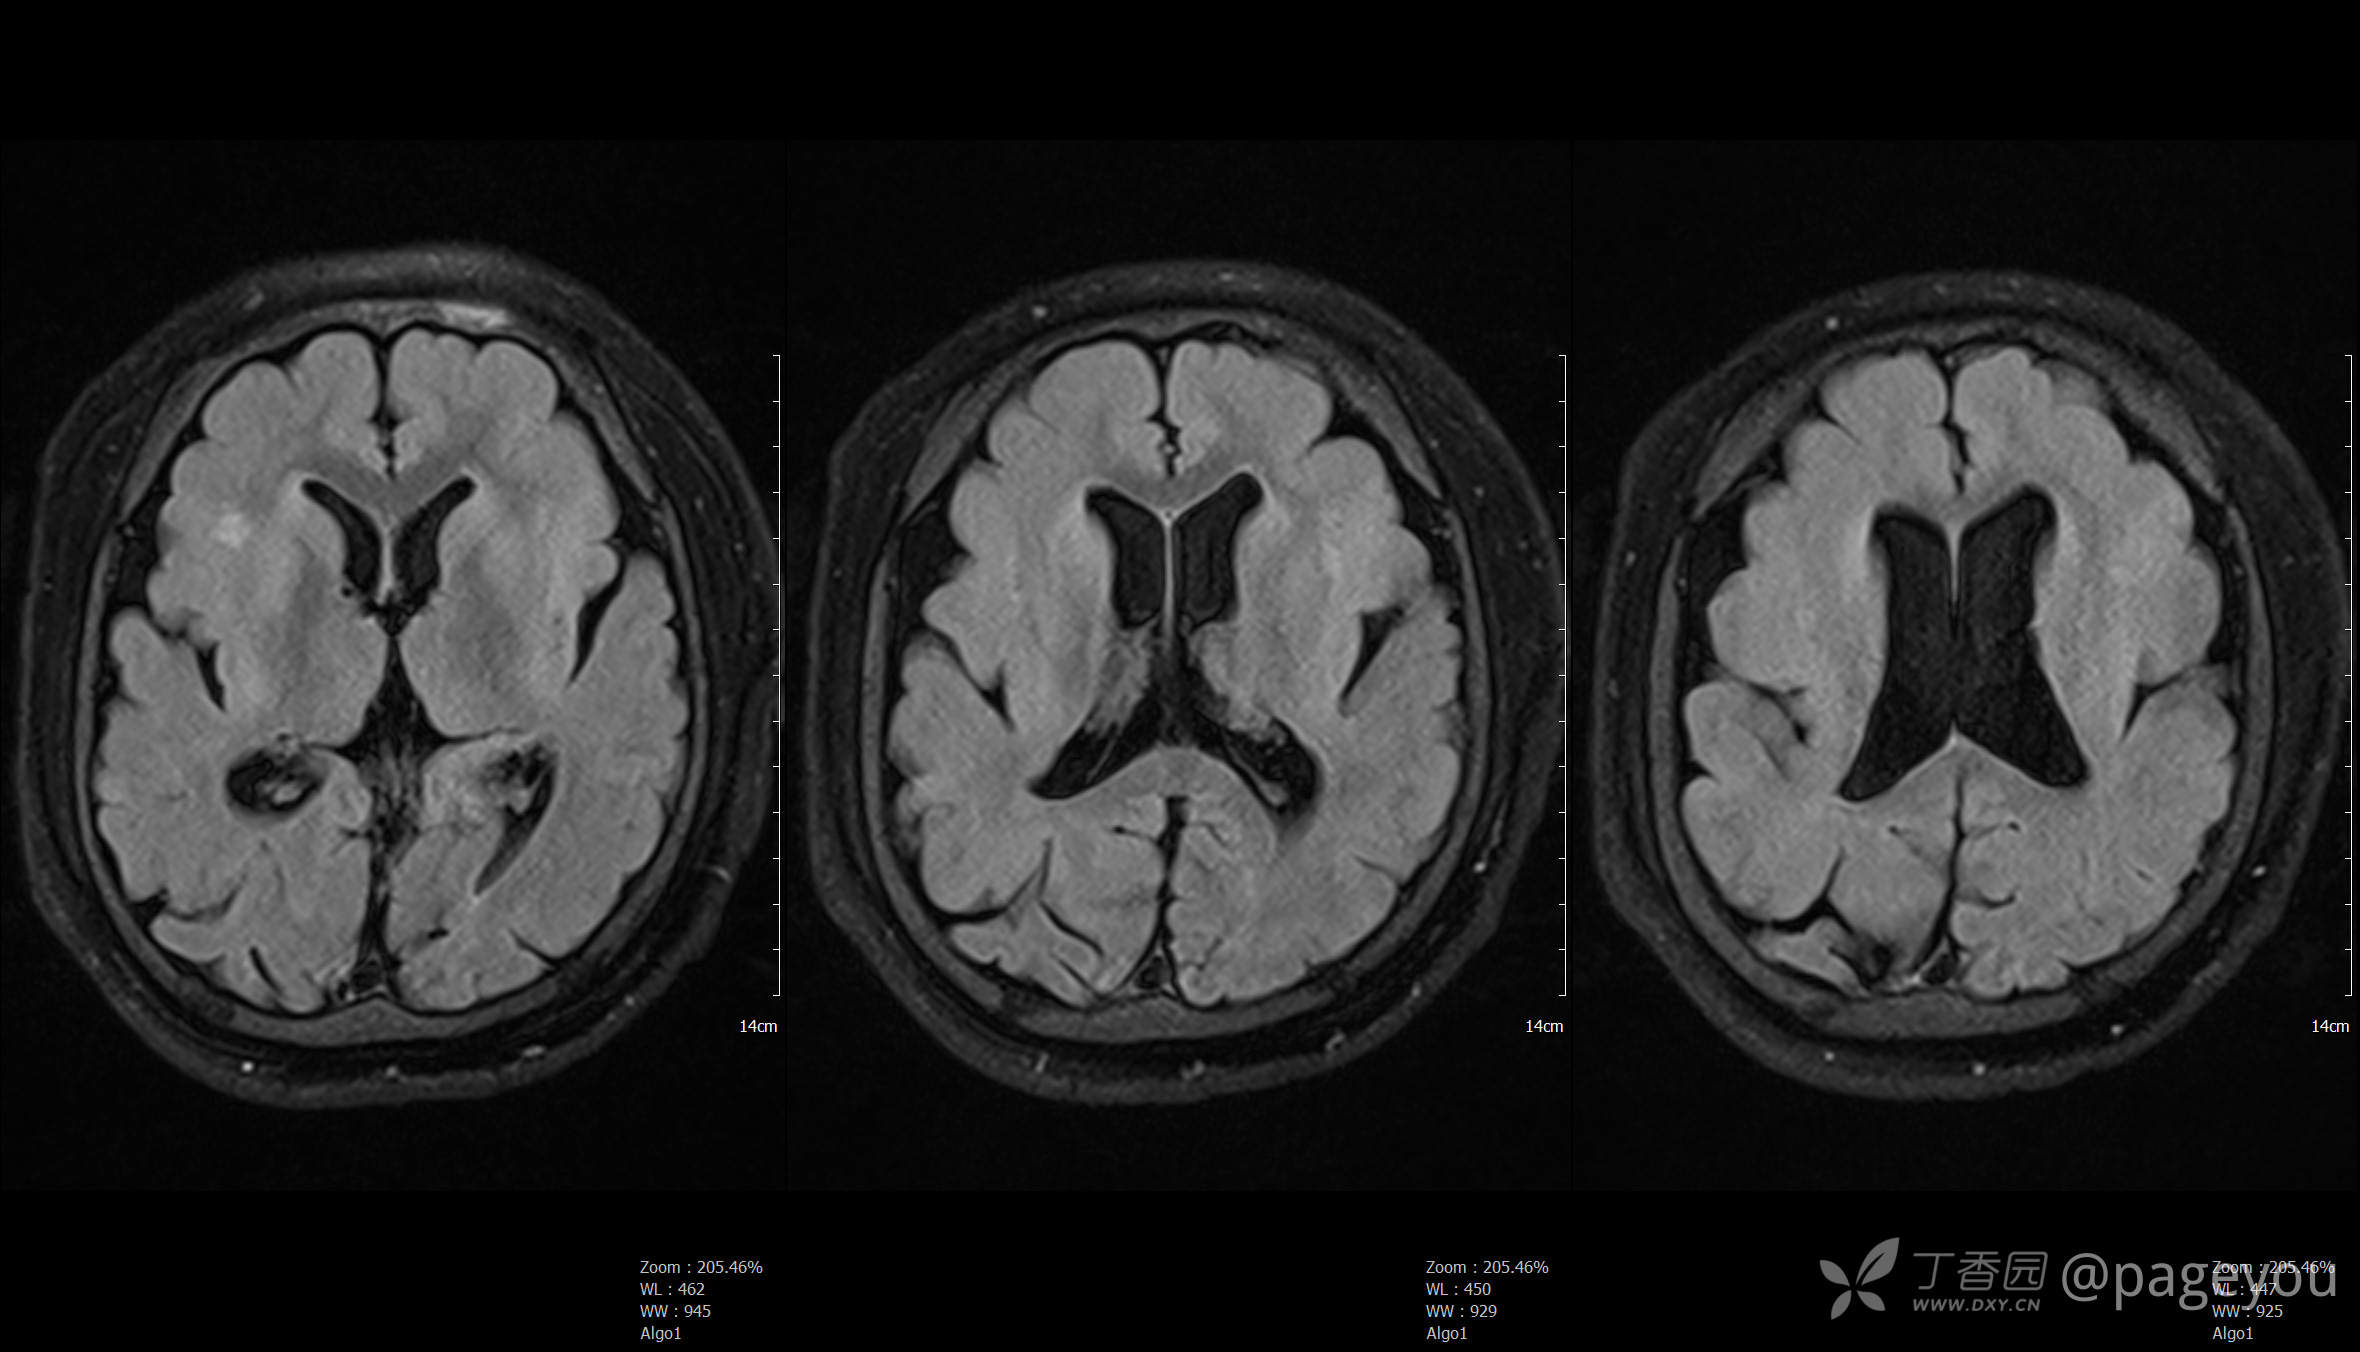

头颅MRI: